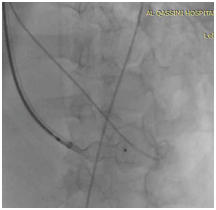

Patient deteriorated rapidly so intra-aortic balloon pump IABP and high doses of inotrops were started. We planned to closed this VSD by device in the catheterization laboratory on the same time but unfurtunalilly was did not have the suitable VSD dives size and No post MI device at all. Patient was shifted to cardiac intensive care unit for close observation and continue on inotrops, IABP and ventilation waiting for the suitable device. He remined stable slightly and after 5 days we prepared for post MI device closure since we obtained post MI VSD devices. The procedure was done under general anesthesia since the patients sedated and Trans jugular venous approach and femoral artery we created Arterio-venous loop (Figure 2) and throw 12 F sheath a 20 mm post MI VSD device closure was deployed successfully in place according to VSD device closure techniq under the guidance of trans-esophageal echocardiography and fluoroscopy (Figure 3).